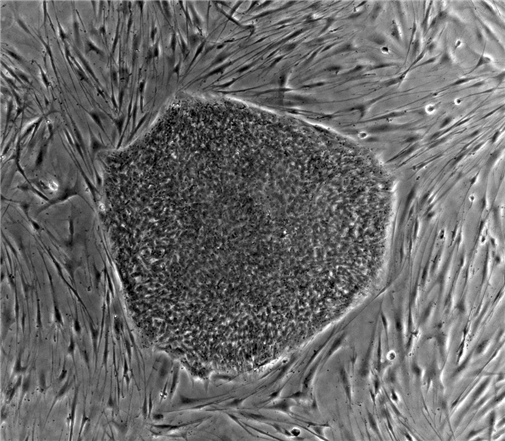

(그림설명: 인간 배아줄기세포)

죽음을 극복함으로 영원히 죽지 않으려는 시도는 인류 역사와 함께 있어 왔습니다. 오늘날 의학은 프로메테우스에게 받은 불처럼 신기하고 놀라운 일들을 인류에게 선물했습니다.

아직 특정 세포로 분화되지 않아 어떤 세포나 조직으로도 만들어질 수 있는 세포에 대한 연구는 손상된 장기를 회복시킬 수 있는 가능성을 열어주었지요.